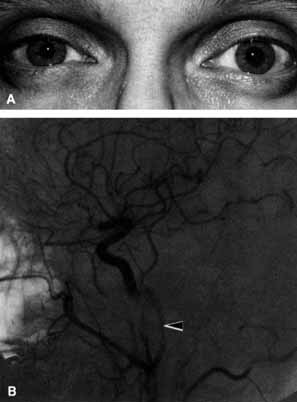

CASE 6

A 40-year-old man developed severe, unrelenting, right-sided headache 1 month after falling from a roof. He noted ptosis and a small pupil coincident with onset of the headache (Fig. 27A). The arteriogram disclosed a narrowed internal carotid artery compatible with the diagnosis of a carotid artery dissection (Fig. 27B).

Fig. 27 A. Right-sided Horner's syndrome (miosis and ptosis) caused by an internal carotid artery dissection. B. Arteriogram demonstrates a narrowed right internal carotid artery (arrow) compatible with a carotid artery dissection.

An example of referred pain and Horner's syndrome is the carotid artery dissection syndrome.49 When the dissection occurs the patient generally develops unilateral referred orbital pain, ptosis, and a miotic pupil but without anhidrosis (see Fig. 27A). Typically, dissection occurs in the older, vasculopathic patient or days to weeks after head trauma. The symptoms are similar to those of cluster headache, that is, recurrent unilateral severe headache and oculosympathetic paresis, the difference in carotid artery dissection being unrelenting pain and unresponsiveness to normal migraine therapy. Arteriogram or magnetic resonance imaging are useful for documentation of the carotid artery dissection (see Fig. 27B).